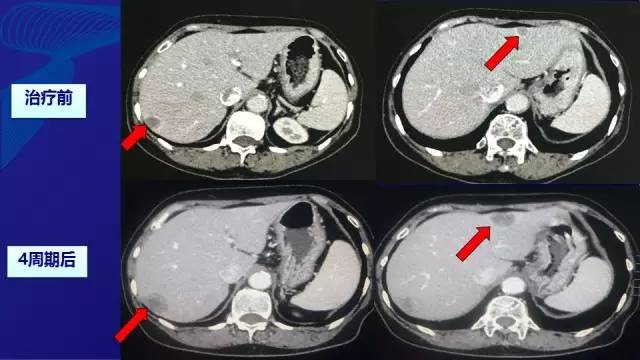

● 2周期—SD; 4周期—PD

● 2015.07行肝转移灶切除术

● 术中见肝II, III段7*6*4厘米质硬灰白色结节,VI段6*5*7厘米质硬灰白色结节,切除肝II,III(2枚)和VI段的肿物(2枚)

● 术后病理:(肝)中分化腺癌,免疫组化符合肠癌肝转移。其中2枚消融病灶坏死成分约80-90%;另两枚病灶坏死成分约30-40%,纤维化约20%。

● 随访23个月无瘤生存